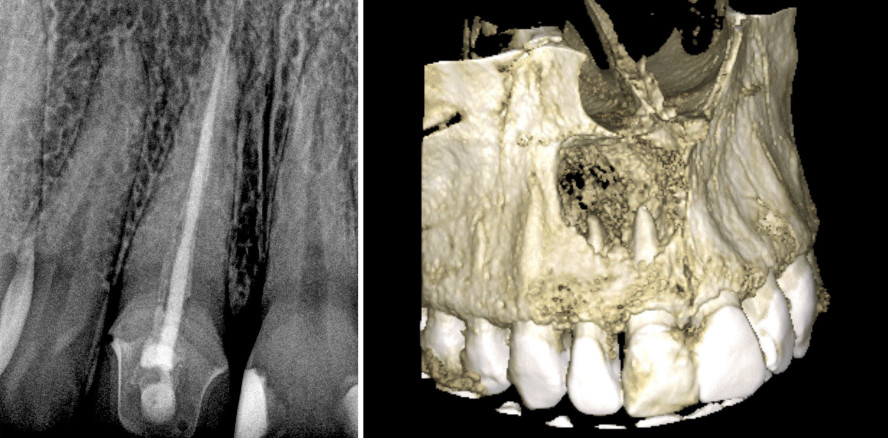

In Anbetracht der generellen Begrenztheit zweidimensionaler Röntgenaufnahmen wird darüber hinaus die Evaluation und Behandlungsplanung besonders interessant.8 Die Autoren Wu et al. zeigten, dass es eine hohe Inzidenz für Zähne gibt, die laut traditionellem Röntgenbild einen gesunden oder heilenden Periapex aufwiesen und nach histologischem Befund und Cone Beam CT (CBCT) eine apikale Parodontitis hatten. Diese Untersuchungen legen nahe, dass selbst die aktuell gängigsten bildgebenden Verfahren bei isolierter Betrachtung irreführend oder falsch sein können (Abb. 1 und 2). Obwohl ein CBCT die Größe einer apikalen Läsion genauer und zuverlässiger erfassen und messen kann, liegen derzeit leider keine Studien vor, die den Einsatz von Computertomografen als Standarddiagnoseinstrument bei periapikalen Läsionen rechtfertigen.2

Nach eingehender klinischer und röntgenologischer Untersuchung wurde eine Pulpanekrose mit chronisch-apikalem Abszess diagnostiziert (Abb. 3 und 4). Die Sondierung der bukkalen Fistelöffnung führte bis zum Apex. Da es nicht möglich ist, die Histologie einer apikalen Radioluzenz dieser Größe zu kennen, war die endodontische Behandlung das Mittel der Wahl, obwohl die Furkation sondiert werden konnte, was die parodontale Situation weniger vorhersehbar machte. Die Entscheidung basierte letztlich u. a. auf der Tatsache, dass eine Wurzelkanalbehandlung weit weniger komplex sein würde als die Extraktion mit anschließender kieferorthopädischer, implantologischer und prothetischer Versorgung.